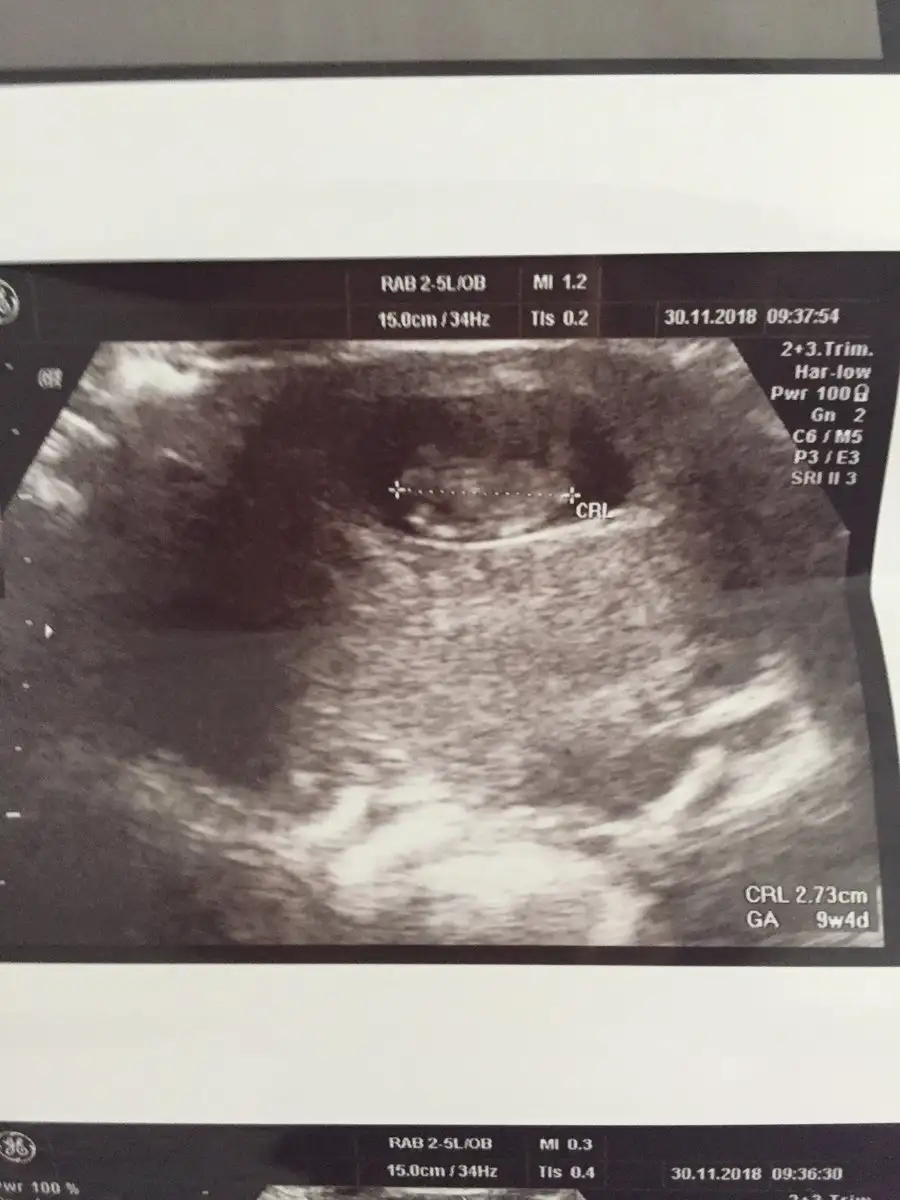

Slm bugün kontrolümüz vardı 10haftalık olmuş bebeğim 12.hafta 2li test için yeniden gidicem.bugün 2li test olur sanmıştım düşük sonrası hemen hamile kaldığımdan adet tarihi sıkıntılı ama en azından tahmini adet tarihine göre gelişim güzel ilerliyor

Resim yükledim kızlar ama ben bu usg Fotoğraflarından hiç bişi anlamıyorum başını poposunu bile ayıramıyorum ki nerde cinsiyet tahmini anlayanlardan yorum bekliyorum

Eki Görüntüle 2210747 Slm bugün kontrolümüz vardı 10haftalık olmuş bebeğim 12.hafta 2li test için yeniden gidicem.bugün 2li test olur sanmıştım düşük sonrası hemen hamile kaldığımdan adet tarihi sıkıntılı ama en azından tahmini adet tarihine göre gelişim güzel ilerliyor